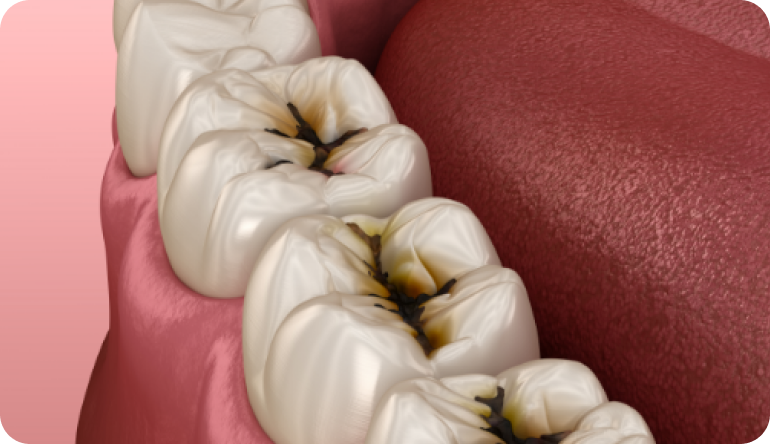

잇몸치료

잇몸치료

잇몸치료

치태 및 치석 제거를 통해 부종, 발적이 생긴 잇몸과 치주조직의 염증을 완화시키고, 치아의 바탕이 되는 치주에 더 이상 질환이 진행되지 않도록 막아줍니다.